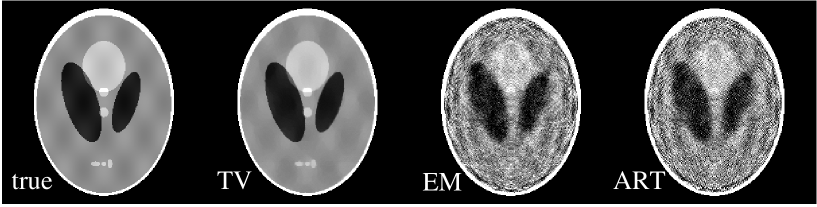

The first case is a reconstruction problem from few-view projections in fan-beam CT. Using the Shepp-Logan phantom shown in Fig. 4A, we generated projection data at 20 view angles specified by:

Though sparse, the angles cover 360∘ about the object. The shift in the second half of the angular measurements helps to reduce redundancy in the scanned data. The total number of measurement rays is , but only 8,236 of these projection elements are non-zero. This number is larger than the twice the support of the gradient image, but it is well below the support of the Shepp-Logan phantom itself. In addition, the angular direction is severely undersampled.

From the projection data generated at the 20 views, we reconstructed images, as shown in row one of Fig. 4, by use of the TV, EM, and ART algorithms. The number of iterations for each algorithm was 200. For a quantitative comparison, we also compare the image profiles along the central lines of the images in the horizontal and vertical directions. The results in Fig. 4 indicate that the TV reconstruction is visually indistinguishable from the true image, suggesting that the system matrix corresponding to sparse fan-beam data may have the ERP even though the column vectors of the system matrix do not form an ortho-normal basis. The EM and ART results show considerable artifacts.